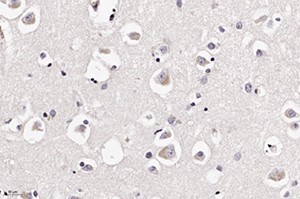

Рисунок 2. Центральный хроматолиз в ядрах нейронов (окраска по методу Клювера — Барреры, ґ200).Вокруг таких сосудов формировались воспалительные инфильтраты, представленные лимфоцитами, сегментоядерными лейкоцитами и обилием белков плазмы.

В периваскулярных астроцитах и ганглиозных клетках определялись аналогичные внутриядерные вакуоли с базофильными включениями (см. рис 2 и рис. 3).

При ИГХ обнаружено наличие антигена вируса в клетках нейронов и астроцитов (см. рис. 5 и рис. 6). В то же время реакция к S-гликопротеину вируса SARS-CoV-2 поверхностных рецепторов была отрицательной.

Рисунок 6. Экспрессия антигена в ганглиозных клетках (ИГХ (anti-SARS-CoV-2 nucleocapsid protein antibody), ґ200).Также в нашей практике встречались случаи полирадикулоневрита (2 наблюдения), где отмечено преимущественное поражение периферических нервов с набуханием и распадом миелиновых оболочек, которое сопровождалось круглоклеточной воспалительной инфильтрацией периневральных оболочек.